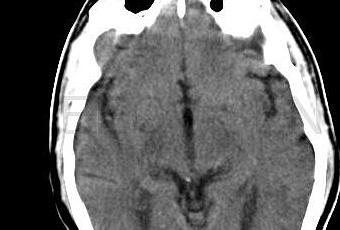

ResultadosDebido a los resultados, se suspendió la incorporación de pacientes después de la aleatorización de 451 pacientes.De estos 451 pacientes aleatorizados, 227 fueron asignados al grupo de tratamiento médico y 224 al grupo ATPS. No hubo diferencias significativas en las características de los pacientes de ambos grupos al inicio del estudio.Criterios de valoraciónLos datos siguientes se basan sobre todos los episodios adversos hasta el 28 de abril, 2011, cuando el último paciente incorporado al estudio finalizó la evaluación de 30 días.Criterios de valoración principales dentro de los 30 días de la incorporación. La probabilidad de que se produjera el criterio de valoración principal fue del 14,7% (33 pacientes) en el grupo ATPS y del 5,8% (13 pacientes) en el grupo de tratamiento médico (P = 0,002). Hubo 5 muertes relacionadas con ACV en el grupo ATPS (2,2%) y una muerte no relacionada con ACV en el grupo de tratamiento médico (0,4%). Un total de 10 de los 33 ACV en el grupo ATPS (30,3%) y ninguno de los 12 del grupo de tratamiento médico fueron hemorragias cerebrales sintomáticas (P = 0,04 prueba exacta de Fisher).

De los 33 ACV producidos en el grupo ATPS dentro de los 30 días de su incorporación al estudio, 25 fueron dentro del primer día del procedimiento y 8 fueron 2-6 días después. La tasa de ACV a los 30 días entre los pacientes sometidos a ATPS fue del 13,5% en las instituciones que incorporaron a más pacientes y del 14,7% en las otras instituciones (P = 0,77).Criterios de valoración principales más allá de los 30 días. Pasados los 30 días, se produjeron ACV isquémicos no mortales en el territorio de la arteria estenosada en 13 pacientes de cada grupo. La probabilidad de sufrir alguno de los criterios de valoración principales durante el período de seguimiento fue significativamente diferente entre ambos grupos terapéuticos (P = 0,009), con tasa del criterio de valoración principal al año del 20,0% en el grupo ATPS y del 12,2% en el grupo de tratamiento médico. Criterios de valoración secundarios y otros episodios adversos. Las tasas de cualquier ACV o de cualquier hemorragia importante fueron significativamente mayores en el grupo ATPS que en el de tratamiento médico. La tasa de muerte o de cualquier ACV (16,3% vs. 23,2%) no mostró diferencias significativas (P = 0,06).

Discusión y conclusionesContrariamente a lo que los autores suponían, los resultados de este estudio mostraron que el tratamiento médico intensivo fue superior a la ATPS con el stent Wingspan en pacientes de alto riesgo con estenosis intracraneal, porque la tasa de ACV cercano al procedimiento tras la ATPS fue mayor que lo esperado, mientras que la tasa de ACV en el grupo de tratamiento médico fue menor. La tasa de ACV o muerte a los 30 días en el grupo ATPS (14,7%) es considerablemente mayor que las informadas anteriormente con el empleo del stent Wingspan (4,4%- 9,6%). La tasa de este estudio no refleja la inexperiencia de los neurocirujanos, ya que la mayoría de ellos también participaron en los estudios anteriores. Una explicación posible es que todos los pacientes de este estudio tenían estenosis del 70-99% y síntomas recientes, mientras que en los registros anteriores los pacientes tenían estenosis del 50- 99% y síntomas que habían aparecido más de 30 días antes de su incorporación al estudio. Los síntomas recientes podrían ser un marcador de inestabilidad de la placa, que aumentaría el riesgo de embolia distal durante la colocación del stent, como sucede con el stent carotídeo extracraneal. Otra explicación de la mayor tasa de ACV tras la ATPS en este estudio es que el protocolo riguroso para evaluar los episodios quizás haya detectado algunos ACV más leves no detectados en los registros anteriores. La diferencia entre los grupos terapéuticos en la tasa del criterio de valoración principal se debe a los episodios tempranos, ya que las tasas de episodios después de los 30 días son similares entre ambos grupos. Sin embargo, menos de la mitad de los pacientes han tenido más de un año de seguimiento. Por lo tanto, el seguimiento prolongado de los pacientes incorporados al estudio será importante para determinar la evolución a largo plazo en ambos grupos.En conclusión: en pacientes con estenosis arterial intracraneal, el tratamiento médico intensivo fue superior a la ATPS con el stent de Wingspan, porque el riesgo de ACV temprano tras la ATPS fue alto y también debido a que el riesgo de ACV con el tratamiento médico intensivo solo fue menor que lo que cabría esperar.